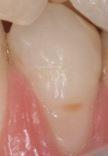

Developmental staging of carious lesions is pivotal for appropriate ethical clinical decision-making in contemporary caries management. Accurate assessment of lesion extent/severity (staging) and activity (grading) allows practitioners to provide the most appropriate preventive advice and suitable interventions, enabling the implementation of evidence-based, person-focused, prevention-based, team-delivered and susceptibility-related phased minimum intervention oral care. Minimally invasive dentistry remains an important operative interventive option for cavitated lesions, but intervening at the right stage ensures patients are not started on an irreversible, destructive restorative cycle unnecessarily. This article provides an update on recommended practical methods for staging the extent/severity and grading the activity of dental carious lesions, especially for those clinical teams delivering primary care and needing to navigate remuneration systems.

龋病损的发展阶段对于当代龋病管理中适当的伦理临床决策至关重要。准确评估病变范围/严重程度(分期)和活动度(分级)可使从业者提供最合适的预防建议和适当的干预措施,从而实施基于证据、以患者为中心、基于预防、团队提供和易感性相关的分阶段最小干预口腔护理。微创牙科仍然是对龋洞性病变的重要手术干预选择,但在正确的阶段进行干预可确保患者不会不必要地开始不可逆、破坏性的修复循环。本文提供了一种更新的方法,用于分期评估龋病损的范围/严重程度和分级病变活动度,特别是对于那些提供初级保健且需要导航薪酬系统的临床团队。